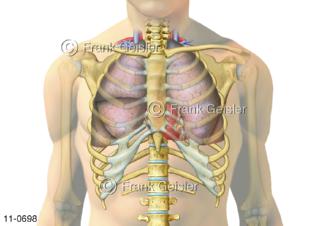

11-0698 Rumpf mit Brustkorb, Lage Atmungsorgan Lungen und Herz